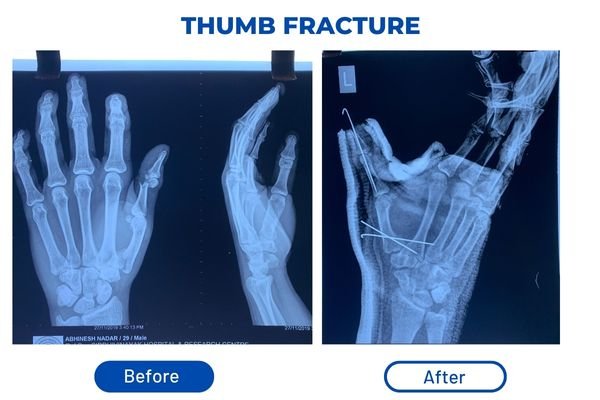

• Surgically inserted metal rods or plates